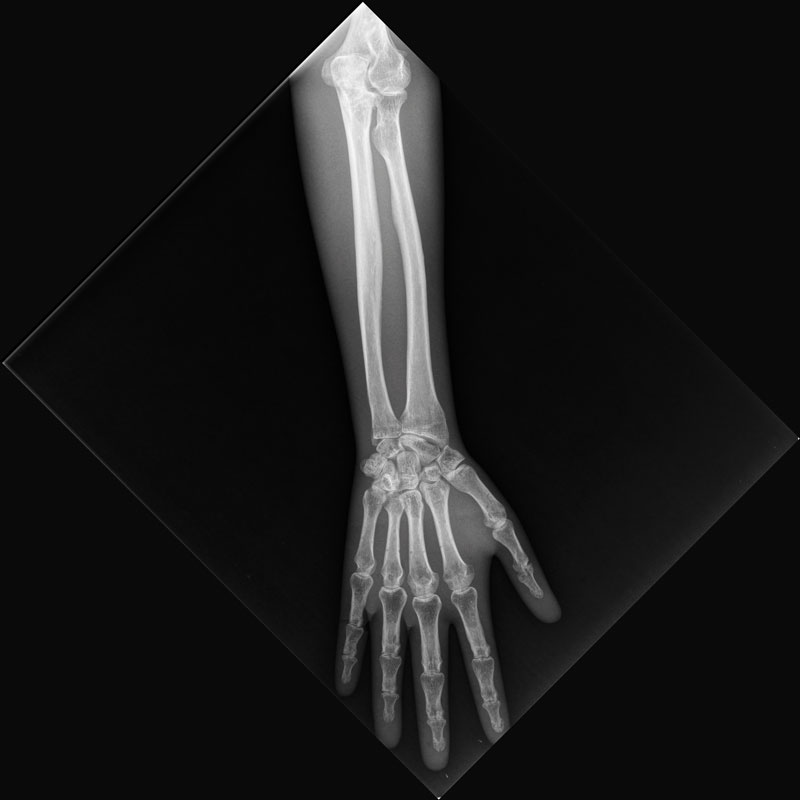

Röntgenphantom Hand mit Unterarm, transparent

Unsere weltweit einmaligen Röntgenphantome enthalten echte menschliche Skelett - Teile. Dies gewährleistet erstklassige Aufnahmen und realistische Übungsbedingungen. Eine praxisnahe Röntgen - Ausbildung ist ohne diese Modelle nicht möglich. Jedes Modell wird in handwerklicher Einzelstückfertigung hergestellt und ist jeweils ein Unikat. Bedingt durch die Verwendung von echten Knochen und die individuelle Fertigung weichen die einzelnen Modelle in Größe und Beschaffenheit voneinander ab. Auch erhältlich in undurchsichtiger Ausführung (opak), Art.Nr. 7225.

7220

3.252,10 € (3870,00 €)

7225

Röntgenphantom Hand mit Unterarm, Opak

1.889,92 € (2249,00 €)